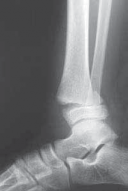

TECH FIG 3•

Tillaux fracture treatment.

A,B.

Tillaux fractures are often not seen clearly on plain radiographic views, and it is important to obtain a mortise view to see the fracture fragment that is obstructed by the fibula in standard AP views.

C,D.

CT scans often aid in fracture characterization and operative planning.

E,F.

These fractures are fixed with compressive interfragmentary cancellous screws across the fracture site, without concern for transphyseal fixation as these patients are always

E F close to skeletal maturity.

TILLAUX FRACTURES: SALTER-HARRIS TYPE III FRACTURES

1. An anterolateral approach to the ankle is used.

2. This fracture can be fixed by a distal-to-proximal, and anterior-to-posterior, compressive interfragmentary cancellous screw (

TECH FIG 3

).

3. Again, cannulated screw fixation may be used if the surgeon prefers it to the use of noncannulated screws.

22. Crossing the physis is not contraindicated in this fracture pattern because by definition the medial physis is closed and complete physeal closure is imminent.